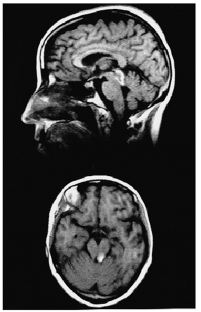

Visuomotor pathways in the vertebrate midbrain mediate rapid, reflexive orienting to abrupt changes. Using the 'inhibition of return' (IOR) mechanism, the attentional system favors novel spatial locations by inhibiting already scanned ones1. In a rare patient with a unilateral lesion restricted to the dorsal midbrain, we demonstrate that IOR is generated within the midbrain superior colliculus.